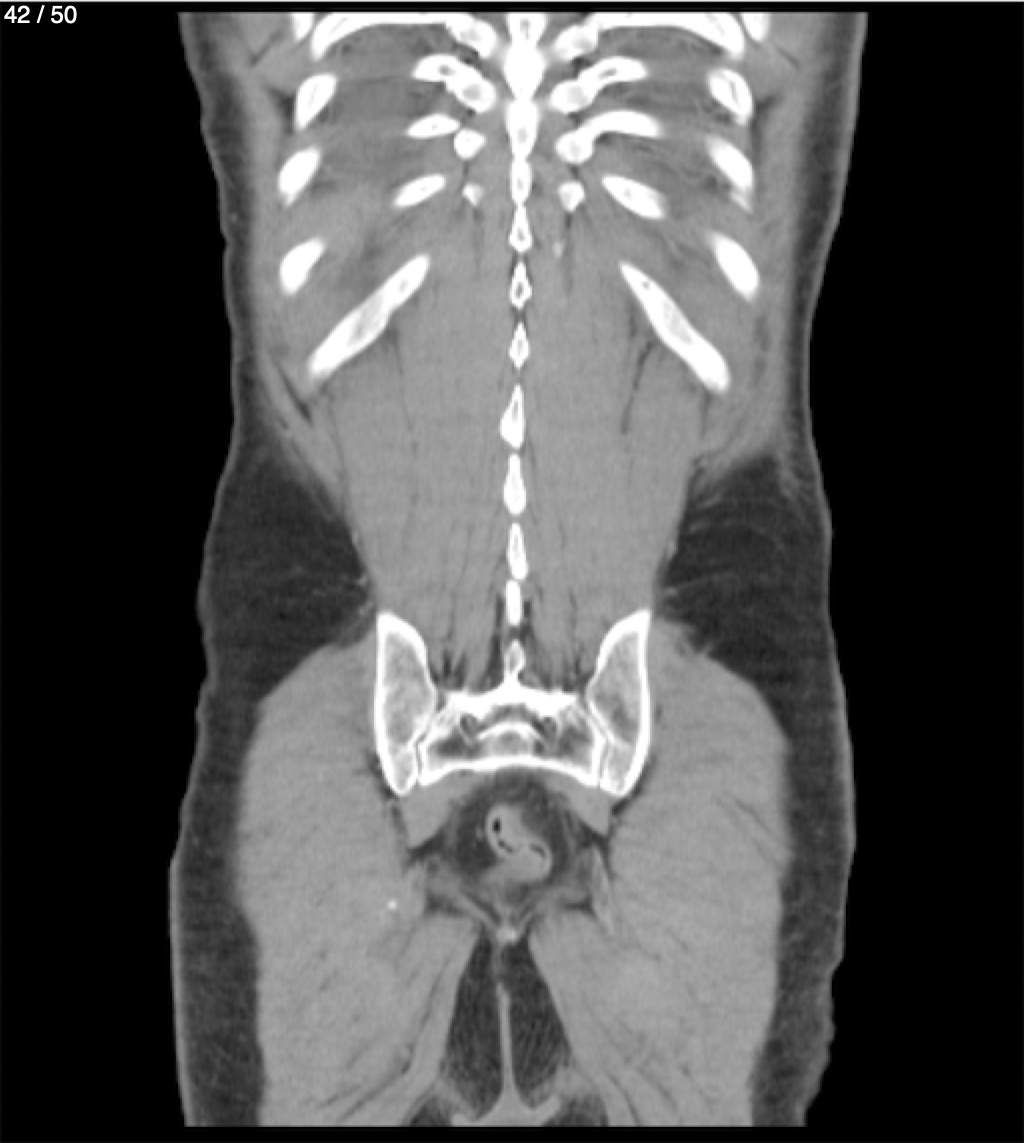

Alonso Victorio Ruiz 62A - T.C Abdomen Syc